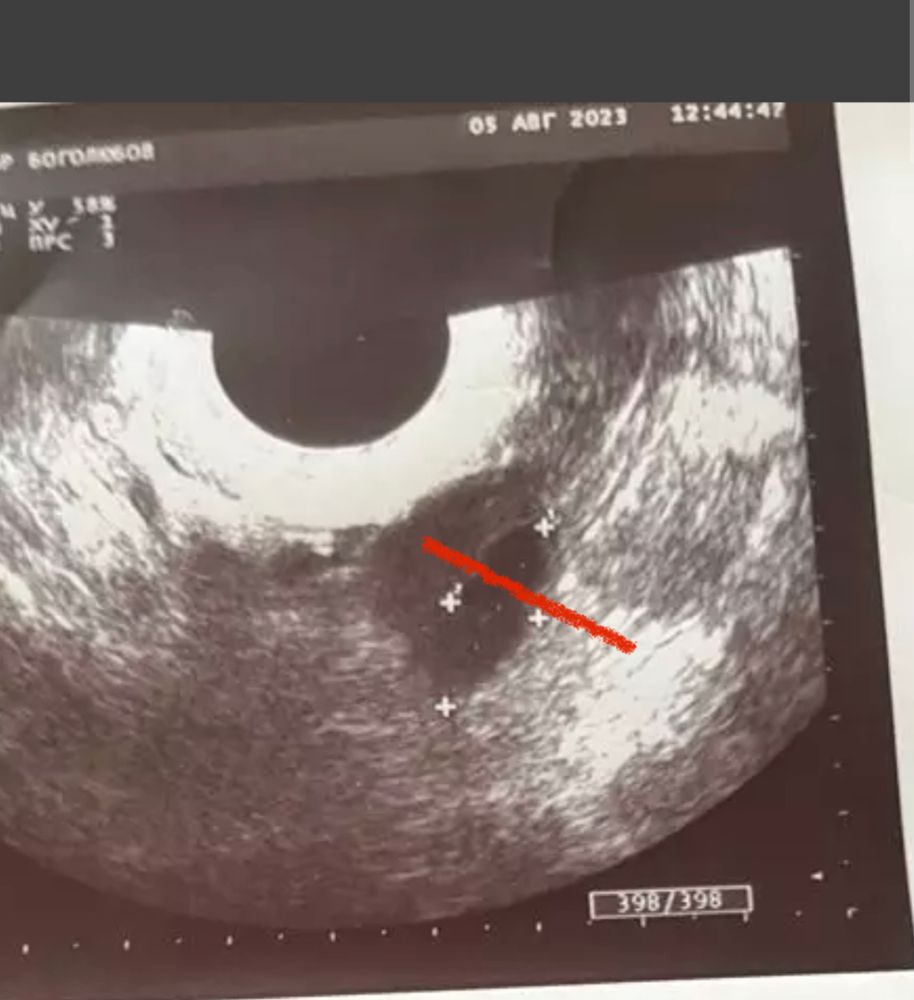

была на узи на 20 дц (так как с мужем ездили в отпуск, не могла сделать раньше) сказали что-то видят в правом и левом яичниках. Вроде как доминантные фолики, а вроде и желтое тело, или вообще «может это дырочки после дриллинга». Этот узист вызвал у меня недоверие, я пошла на сл. День в другую клинику и сделала узи там. Врач сказала, что не видит никаких ДФ и что овуляции вообще не было, и жидности в позадиматочном пространстве нет. Эндик всего 6мм. Узи подкрепляю. Третье фото это узи на 21дц. Подскажите пожалуйста, что это было?

Первый узист, похоже, принял два фолликула за один большой, разделила их на маленькие как мне кажется